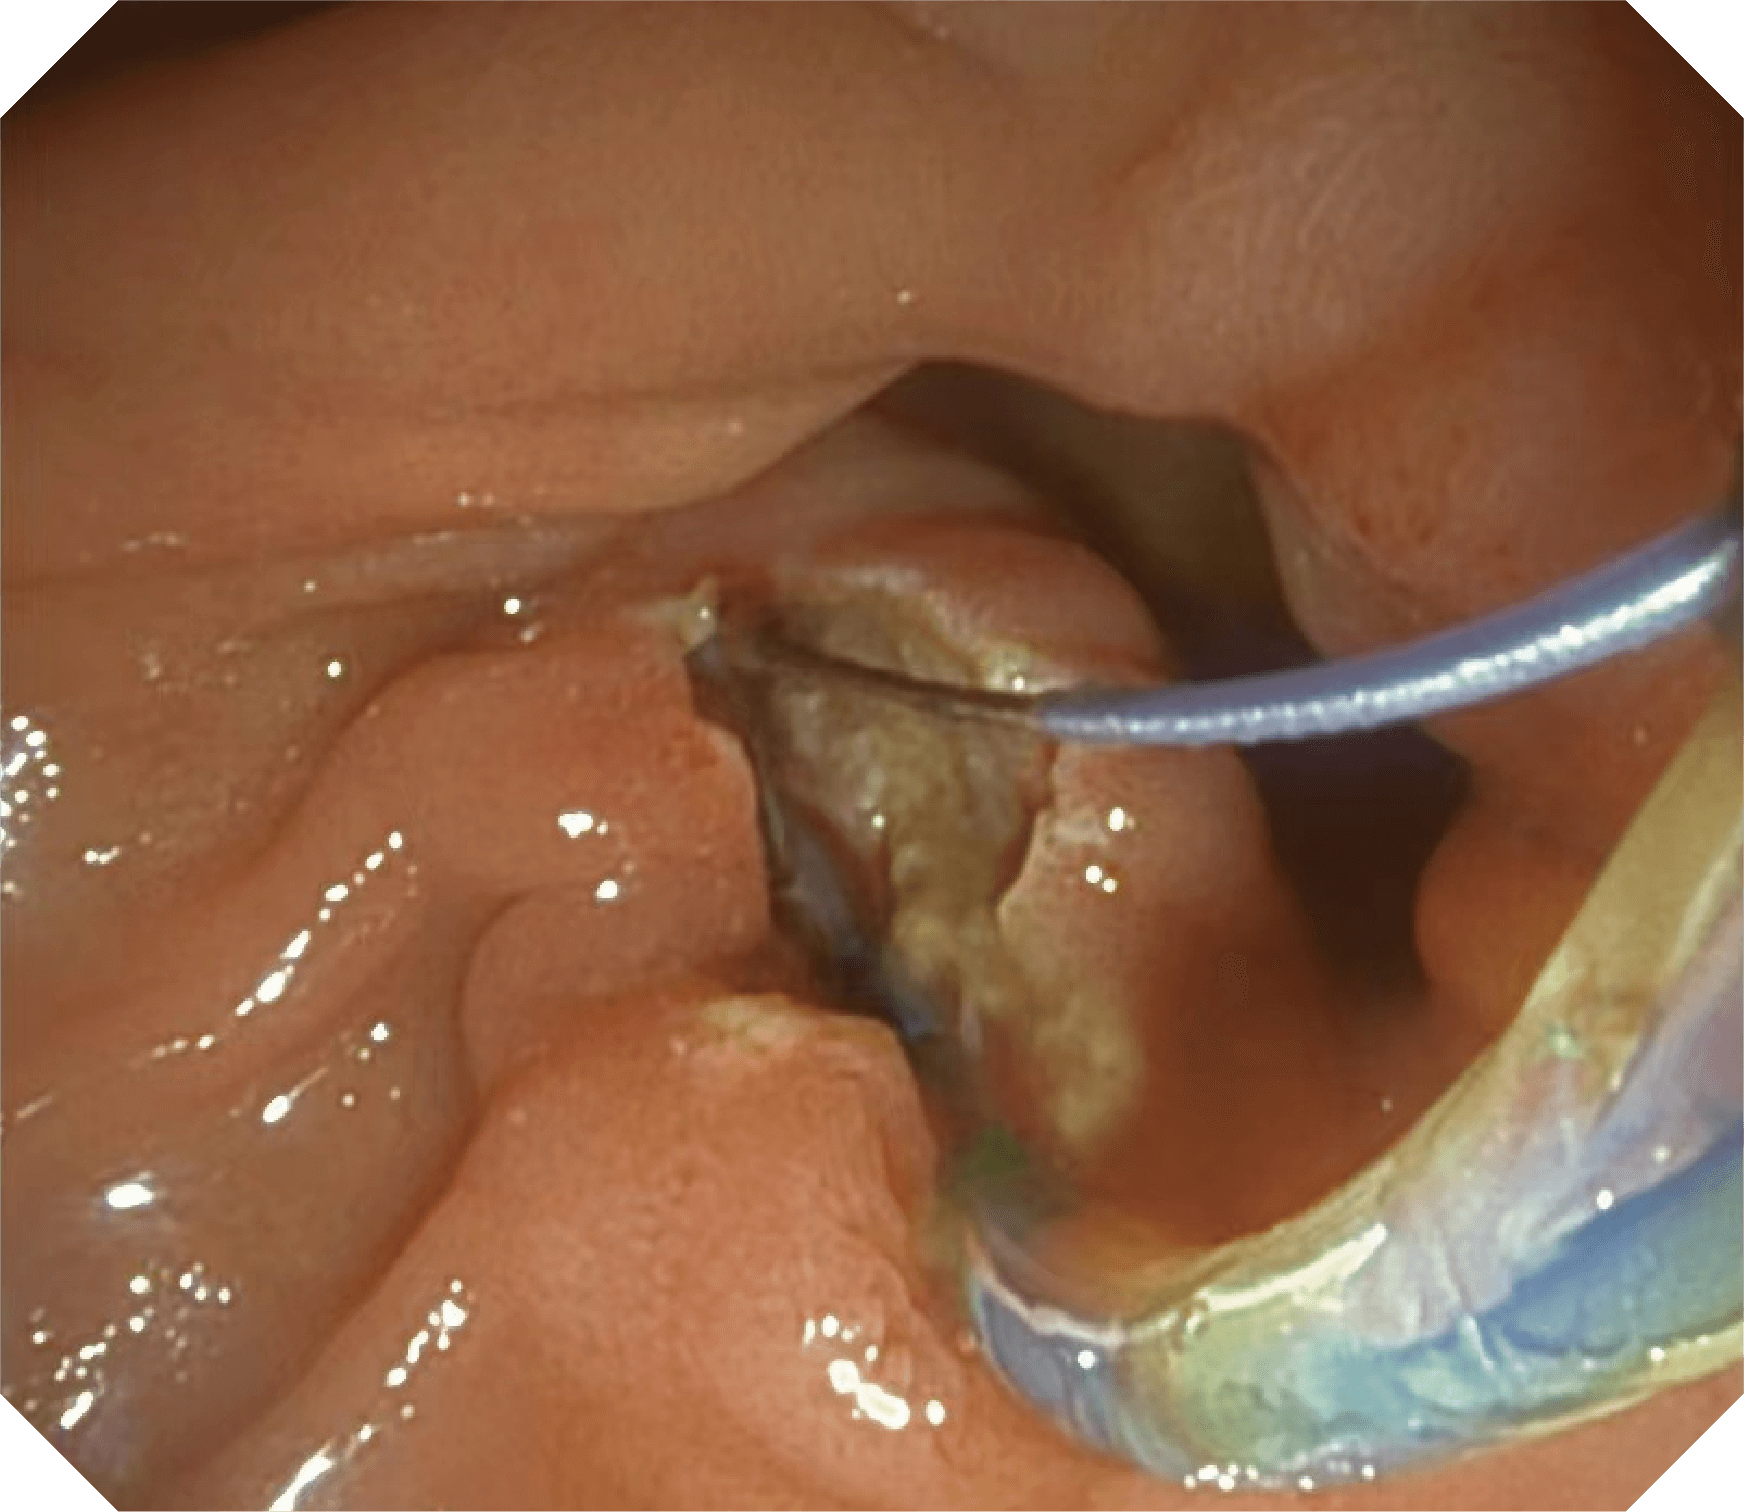

导丝机械锁紧功能

V槽设计提升导丝控制